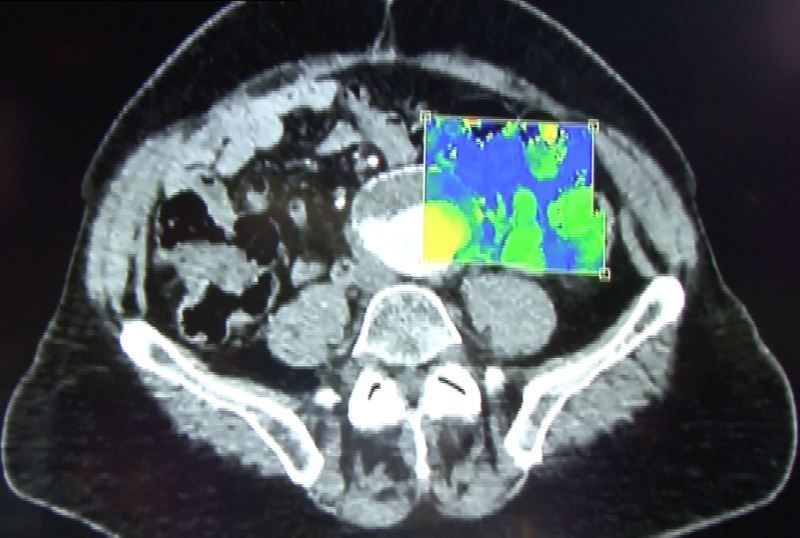

Philip's spectral CT showing how the system can identify the atomic number of iodine and calcium from photons on the scan and overlay a color map showing the chemical composition of materials in the body. This image shows a traditional grayscale Hounsfield image of a vessel and the right image showing a spectral version showing color-coded iodine and calcium.

Using a type of spectral analysis, the system can separate out materials made up of specific atomic numbers off the periodic chart of elements. The system so far has been tested for iodine and calcium. This can be used to help differentiate between areas of high blood contrast uptake and calcified areas, which can be useful in diagnosing kidney stones and better delineating various types of atherosclerotic plaque in arteries. Elements can be assigned specific color codes to make them standout on scans, even if the surrounding tissue has similar Hounsfield unit numbers.